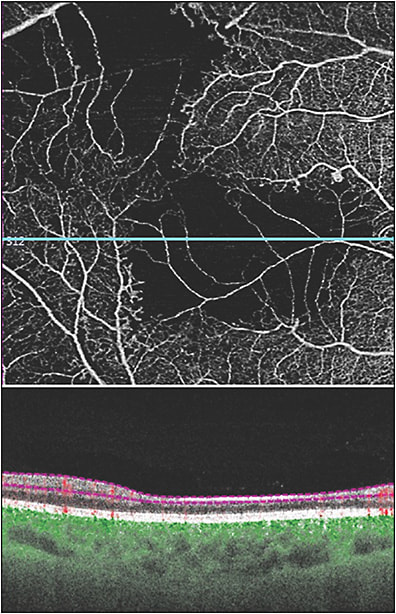

Regarding new terminology, there are at least 3 new OCTA descriptions of retinal vascular changes that can be identified in DR (Table 2). Disorganization of retinal inner layers (DRIL) occurs in eyes with ischemic changes in diabetic retinopathy and is characterized by loss of boundaries between the ganglion cell, inner plexiform, and outer plexiform layers.20 It is associated with morphologic changes in the inner retina, corresponding to more severe DR and poorer visual acuity.21 While exclusively an OCT diagnosis, DRIL can be better identified on SS-OCTA because of the advantage of segmenting different layers (Figure 6). In particular, areas of ischemia on OCTA scans correspond to areas of DRIL as seen on OCT B scans.22 Diabetic macular edema/DRIL can be viewed via B scans, allowing for one imaging modality to evaluate diabetic retinopathy.15

In diabetic patients without clinically apparent retinopathy, OCTA can be used to detect abnormalities in and around the foveal avascular zone, showing subtle abnormalities in capillary perfusion density compared to nondiabetic eyes.13 When comparing OCT metrics in diabetic patients without DR, perifoveal capillary loss in the superficial capillary plexus and inner retinal layer thickness can be identified.24 Measurement of capillary perfusion density on OCTA has been found to be lower in eyes with moderate or severe nonproliferative DR or PDR compared to eyes with no or mild nonproliferative DR.25 Capillary perfusion density (CPD) maps employ color-coded topographic maps with quantitative data to objectively grade and linearly assess the microvascular status of diabetic disease in the 3 layers from the en face OCTA (superficial retinal capillaries, deep retinal capillaries, and choriocapillaris). CPD values have been found to be significantly lower in those with early changes of diabetic retinopathy compared to age-matched controls.10 In nonproliferative DR and PDR, OCTA enables assessment and quantification of perfusion, as well as the ability to identify in which layer the nonperfusion is located within the retinal and choroidal vasculature (Figure 8). However, measurements of vessel density as well as perfusion density are not standardized across different OCTA platforms.26